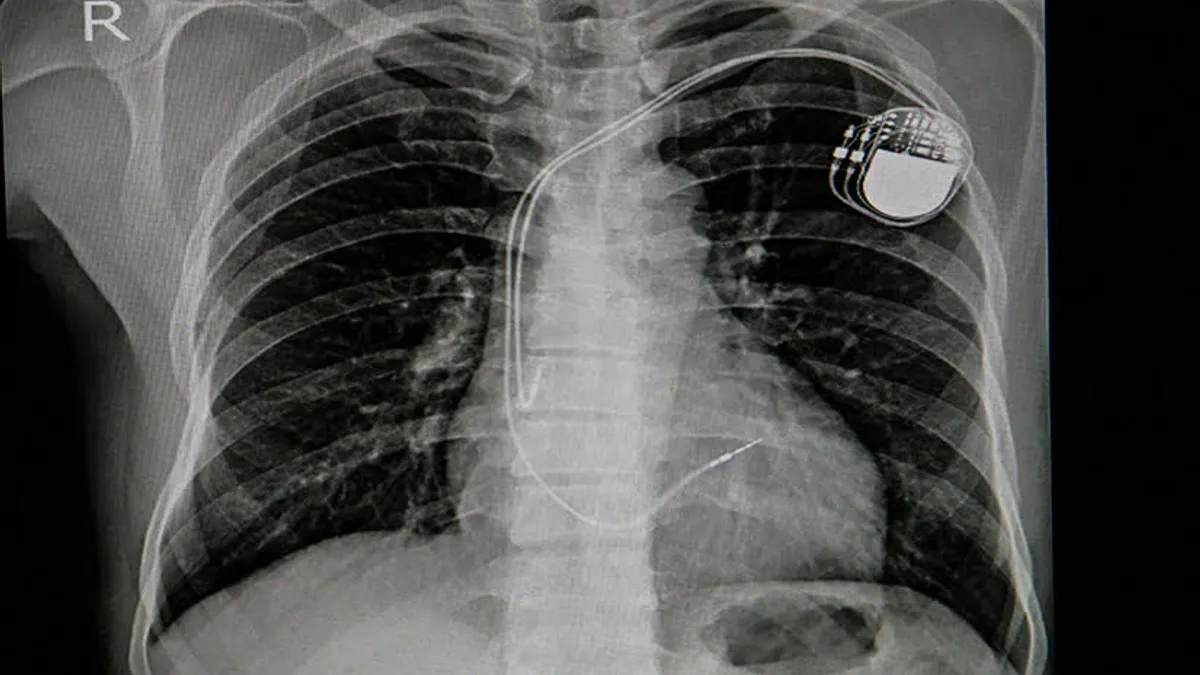

Stimulatoarele cardiace nu se resterilizează, nici refolosesc (sursa: reginamaria.ro)

Stimulatoarele cardiace nu se resterilizează, nici refolosesc. Un comunicat al Ministerului Sănătății a lămurit oficial confuzia din capetele unora: dispozitivele de tipul stimulatoarelor cardiace sunt de unică folosință și refolosirea acestora este interzisă în mod expres.